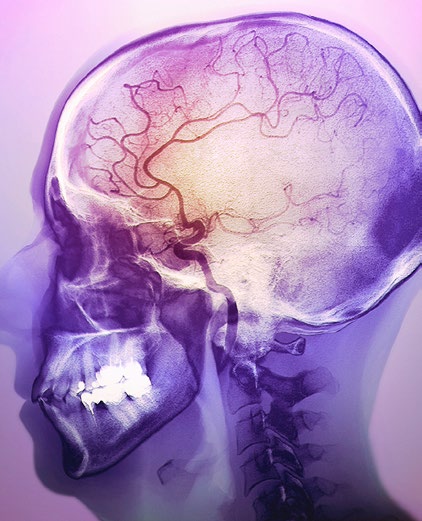

Utvrđena veza između visokog unosa soli i moždanog udara te kardiovaskularne bolesti

Do sada je bilo nedvojbeno utvrđeno kako je povećan unos soli jedan od čimbenika rizika za nastanak hipertenzije, no zahvaljujući radu prof. Pasquale Strazzulla sa Sveučilišta u Napulju te prof. Francesca Capuccia sa Sveučilišta u Warwicku, u Velikoj Britaniji, postaje jasno kako pretjerano zasoljavanje hrane povisuje rizik i za cerebrovaskularne i kardiovaskularne bolesti. Velika metaanaliza, objavljena je u on-line izdanju „British Medical Journala“, a obuhvatila je trinaest publiciranih studija koje zajednički pokrivaju 170 tisuća ispitanika. Njihovo istraživanje jasno pokazuje kako smanjenje dnevnog unosa soli za jednu čajnu žličicu (5 g) smanjuje rizik za nastanak moždanog udara za 23% te rizik za kardiovaskularne bolesti za 17%. Na temelju ovih podataka, autori smatraju kako bi smanjenje dnevnog unosa soli za jednu čajnu žličicu dnevno preveniralo milijun i četvrt smrti godišnje od moždanog udara i tri milijuna smrti od kardiovaskularnih bolesti godišnje u općoj populaciji. Preporuke Svjetske zdravstvene organizacije su unos do najviše 5 g soli dnevno, no smatra se kako je prosječan unos soli u zapadnim zemljama oko 10 g, dok je u istočnoeuropskim zemljama unos još značajno veći. U zaključku, autori navode kako je ovo još jedan dokaz kako je prekomjerni unos soli važan čimbenik rizika od kardiovaskularnih bolesti. |